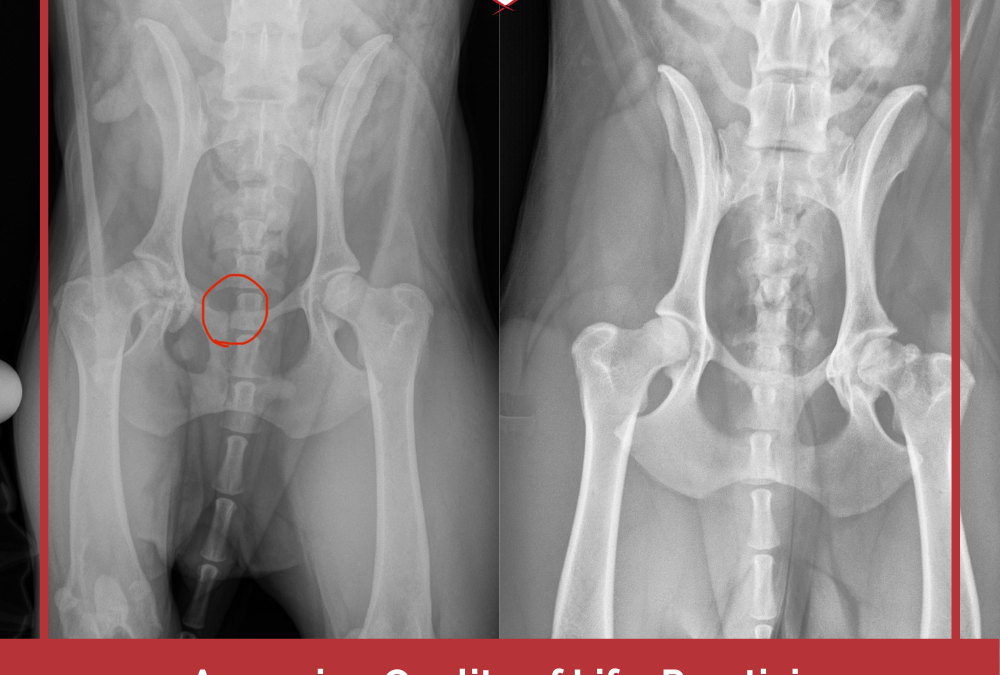

Quality of Life Assessment: Practicing What I Preach

by Kate LaSala | Mar 23, 2026 | Dog Training, Fear, Aggression and Reactivity, Pet Loss & Grieving, Rescue Dogs, Resource Guarding

A little over a year ago, we adopted a new dog, Gertie. Full name: Gertrude Wigglebottom, because if you’ve seen some of my videos of her…well, it’s obvious. If you’ve been here a while, you might remember that just four days after making her...

Assessing Quality of Life: Practicing What I Preach

by Kate LaSala | Feb 24, 2025 | Dog Training, Fear, Aggression and Reactivity, Pet Loss & Grieving, Rescue Dogs, Resource Guarding

We recently adopted a new dog, Gertie, aka Gertrude Wigglebottom, a little over ten months after we said goodbye to our precious BooBoo. Surprisingly, adopting a new dog dredged up lots of grief feelings about Boo, which I’ll talk about another time. I wanted to...